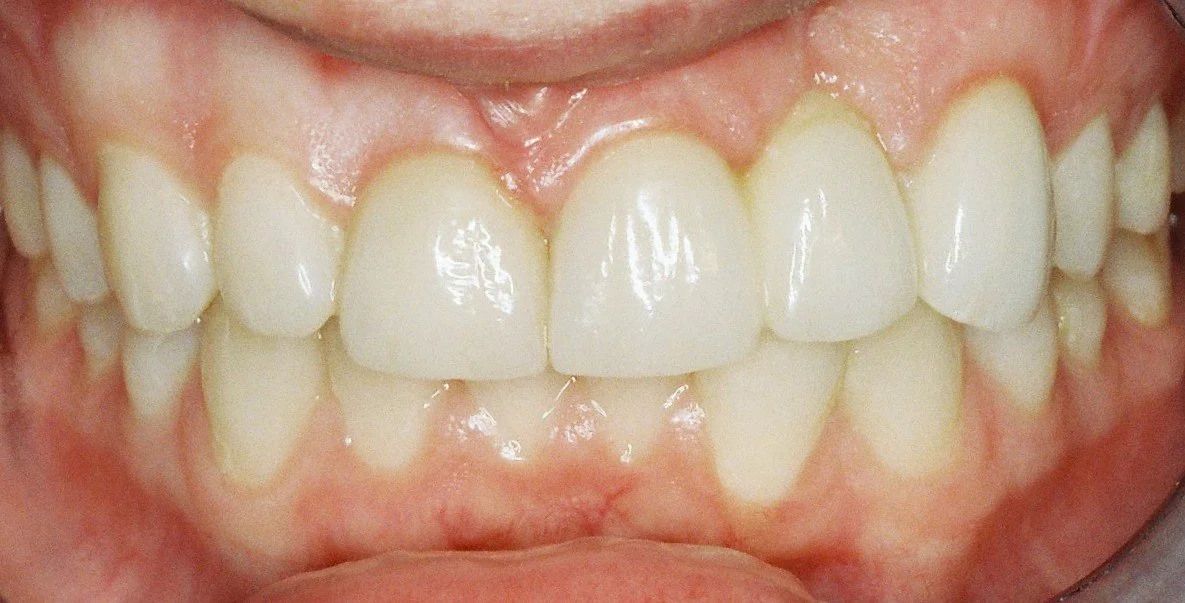

The implant dentures seated in the mouth biting in hinge bite.

The completed aesthetic implant dentures